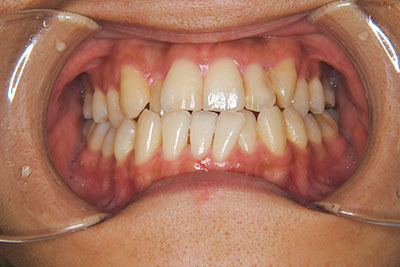

おとなの方でも矯正治療をあきらめないでください!

矯正歯科治療は子供の頃だけしかできない……

子供の頃に比べ大人になったら治療期間がすごく長い……

というようなイメージをお持ちではありませんか?

子供の頃に矯正治療を行う方が治療期間が短く済むというのは、確かですが、矯正治療は患者様の意識も重要です。

いくら歯が動き易くとも、本人がやる気でなければ効果は出ませんし、むし歯発生のリスクも高まります。おとなの方は顎の成長が終わっているため、治療の計画が立てやすいとも言えます。「もう大人だから…」とあきらめず、一度ご相談ください。

本格矯正治療の詳しい説明は小児矯正治療/本格矯正治療ページを御覧ください。